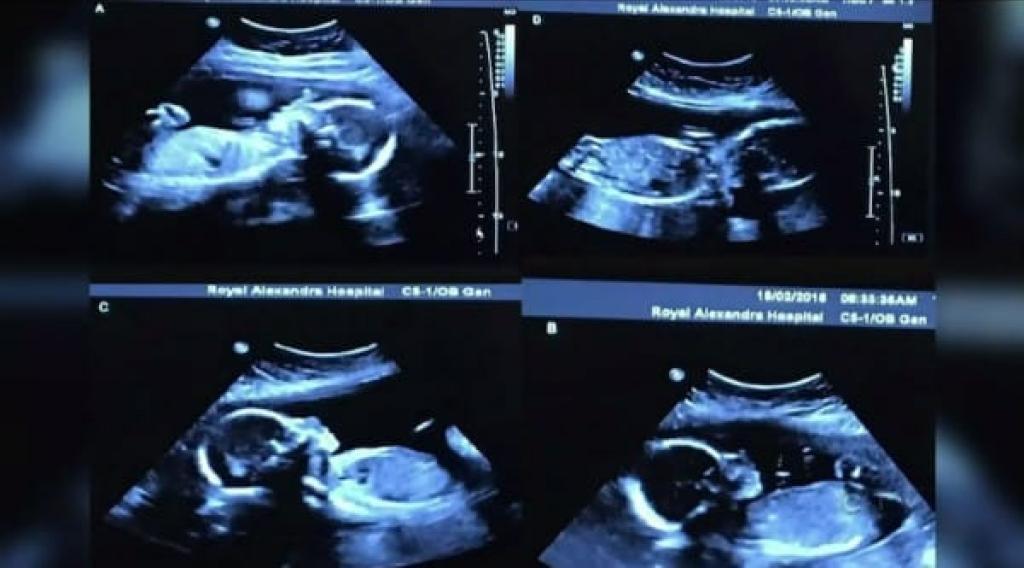

Qual não foi o seu espanto quando, perto do Natal, descobriram que iriam ter quatro filhas, que vão responder pelos nomes de Abigail, McKayla, Grace e Emily!

“Eu fiquei realmente, realmente chocada. Felizmente eu estava deitada, caso contrário, teria certamente caído. Os médicos dizem que é um caso que pode acontecer. Mas que não acontece muitas vezes, é muito, muito raro”, confessou a mãe.